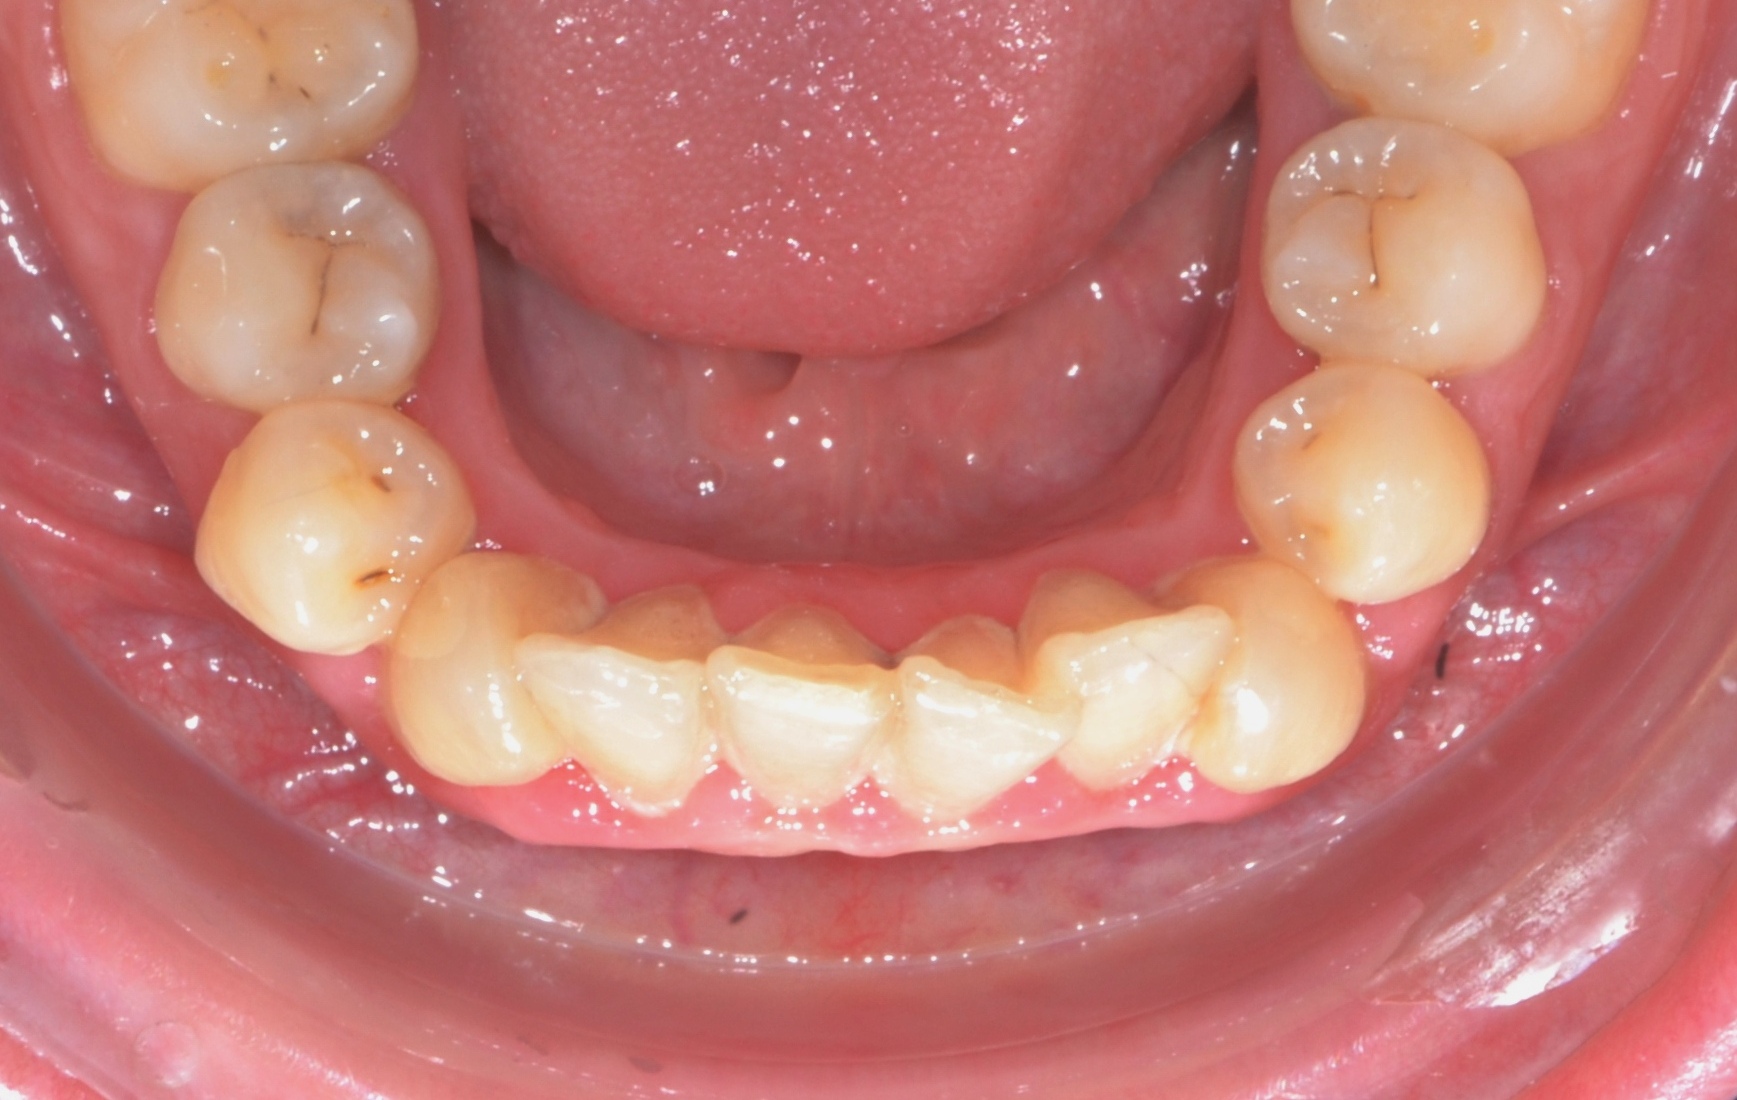

Выявленные проблемы

• Сужение верхнего зубного ряда, сужение и уплощение нижнего

• Глубокий прикус

• Скученное положение 42-32, 12-22

• Дефицит места постоянным зубам

Брекет-система Ultra